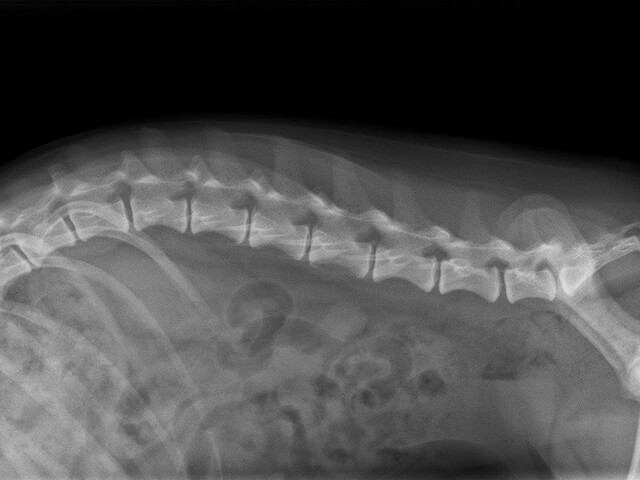

犬の椎間板ヘルニア 犬の椎間板ヘルニア

犬の椎間板ヘルニアとは?

椎間板ヘルニアは、背骨と背骨の間にある椎間板(クッション材)が飛び出し、近くを通る脊髄神経を圧迫する病気です。

これにより、腰の痛みや四肢の麻痺(グレード1〜5)といった症状が出ます。

以前はダックスフンドに多くみられた病気ですが、最近ではフレンチブルドック・ペキニーズ・トイプードル・チワワなど、様々な犬種に好発するとされています。

重症化すると手術が必要なケースが多く、グレードが進行した場合命に関わる可能性もあります。

エコー、レントゲンだとわからないこと エコー、レントゲンだと

わからないこと

CT検査だからわかることレントゲン検査は、椎間板ヘルニア自体を診断することはできませんが、脊椎の骨折や腫瘍など、似たような症状を呈する他の疾患を除外するために必要な検査です。

CT検査だからわかること CT検査だからわかること

CT検査だからわかることCT検査は、脊髄神経を圧迫している椎間板物質の正確な位置や脊髄圧迫の程度を把握できます。

当院ではこれに脊髄造影検査なども組み合わせることでヘルニアの病変部位を特定し、神経学的検査や重症度などを総合して手術に必要な最適アプローチ(術式や手術範囲)を決定しています。